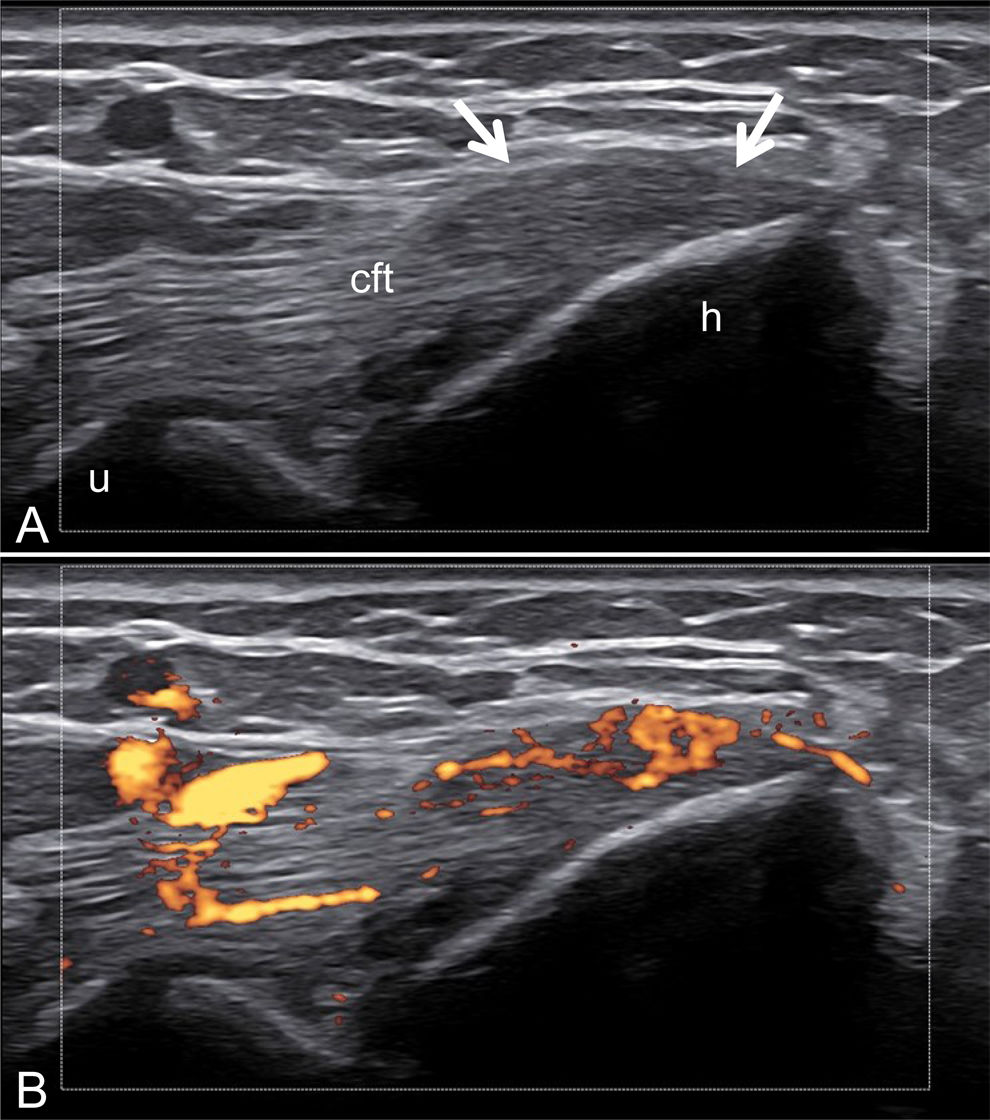

Entesitis (Fig. 3): Clinically, enthesitis is reported in 35–50% of patients with PsA; however, the true prevalence may be underestimated, and more entheseal sites should be assessed, preferably using advanced imaging techniques such as US. Common sites of enthesitis in PsA include the attachment of the plantar fascia and Achilles tendon, patellar tendons, and ligament insertion sites around the pelvis, ribs, and elbow. Moreover, enthesitis often occurs in the spine at ligament insertion sites on the vertebra [39].

OMERACT defines enthesitis as hypoechoic and/or thickened tendon insertion close to the bone (within 2mm of the bone cortex) that shows Doppler signal if active and may exhibit erosions, enthesophytes/calcifications as a sign of structural damage. Lesions should be viewed in two perpendicular planes [23]. There are other elementary US lesions, such as bursitis and fibrocartilage alterations that are not part of the definition proposed by OMERACT; however, they are considered as part of the inflammatory pathology at the level of the entheses [40].

Furthermore, ultrasound reveals structural changes in the finger extensor tendons indicative of enthesitis, further demonstrating the utility of imaging in psoriatic arthritis evaluation (Fig. 8).

Fig. 8.Enthesitis at the Distal Insertion of the Extensor Tendon. Sonographic image obtained using Logiq e US system with an 8–18i MHz linear transducer. Comparative ultrasound images of the extensor tendon at the distal insertion in the same phalanx of both hands. One hand demonstrates significant thickening and hypoechogenicity indicative of enthesitis (B), while the other hand shows no such findings (A). Additionally, the presence of intra-tendinous power Doppler signal in the affected hand is noted as a sign of active enthesitis (C).